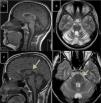

Autosomal recessive spastic ataxia of Charlevoix-SaguenayARSACS is caused by mutations to the SACS gene (13q12.12), which codes for sacsin, a chaperone protein that interacts with the proteasome and is involved in mitochondrial function and axonal and dendritic transport.41 The condition is thought to result from a developmental disorder and a degenerative process.42 It was first described in Quebec; cases have subsequently been reported in all regions of the world. The phenotype of the condition is relatively homogeneous and is characterised by early-onset ataxia accompanied by pyramidal signs, mixed sensorimotor neuropathy, and pes cavus. In some cases of late-onset ARSACS, pyramidal signs are less severe and patients display hearing loss. Examination of the eye fundus may reveal the persistence of myelinated fibres, whereas optical coherence tomography images may show increased thickness of the retinal nerve fibre layer. MRI studies show atrophy of the cerebellar vermis and the posterior part of the corpus callosum, and linear hypointensities in the pons (Fig. 1C and D); diffusion tensor imaging reveals alterations to the pontocerebellar fibres.42,43

MR images. A) Sagittal T1-weighted sequence showing marked atrophy of the cerebellar vermis in a patient with ARCA1. B) Axial T2-weighted sequence showing pancerebellar atrophy in a patient with ARCA1. C) Axial T1-weighted sequence showing atrophy of the posterior part of the corpus callosum in a patient with ARSACS. D) Axial T2-weighted sequence showing linear hypointensities in the pons of a patient with ARSACS.

ARCA1 is caused by mutations to the SYNE1 gene (6q25.2), which codes for nesprin-1, a nuclear membrane protein involved in linking the nucleoskeleton to the cytoskeleton. The condition is usually associated with a slowly progressive pure cerebellar syndrome, with MRI studies displaying evident pancerebellar atrophy (Fig. 1A and B). Onset usually occurs late in the third decade of life.44,45